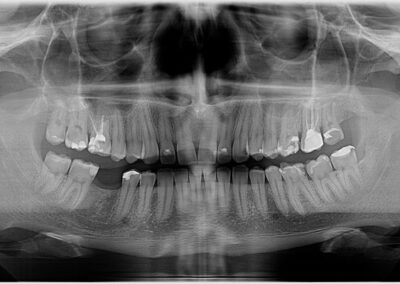

Na rendgen snimcima prikazana je donja vilica pre ugradnje implanta i donja vilica nakon perioda srastanja (oseointegracije) implanta sa koštanim tkivom.